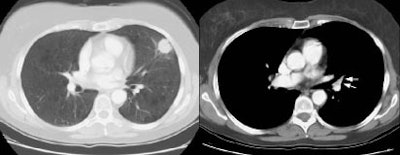

Example 1: False-positive exam -- this patient had a right upper lobe squamous-cell carcinoma. The mass is adjacent to the superior vena cava. Abnormal mediastinal N2 (yellow arrow) nodes were identified by the staging CT exam. Contralateral N3 nodes (white arrows) were borderline abnormal by size criteria. The patient underwent medianstinoscopy and anterior mediastinotomy (Chamberlain procedure) for pre-operative staging -- both of which were negative for malignant cells. The patient had underlying interstitial lung disease which has been associated with the presence of reactive mediastinal adenopathy. At surgery the patient was found to have ipsilateral hilar adenopathy (N1) and parietal pleural invasion (T3 tumor) or a stage IIIA.